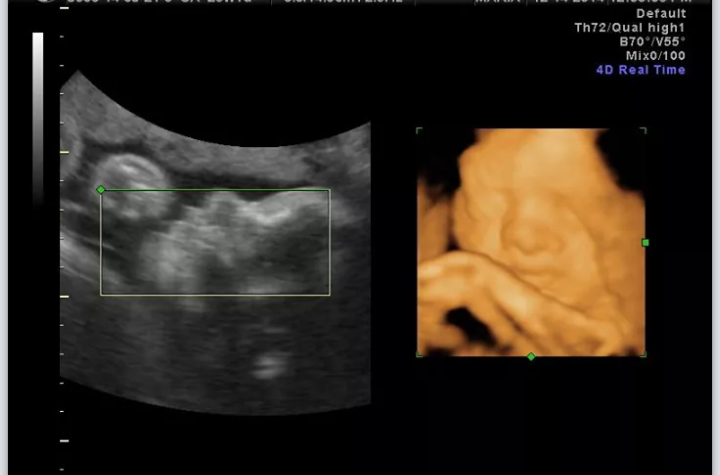

I couldnt sleep because im way too excited for my 3d u/s in a few hours. The more I stare at the 2d u/s where we got to see his lips, the more im like "he looks just like ME!" Haha, im hopeful.

AW: two of the shots from our elective 3d today! The technician said he had my nose and we were able to see the same little ridge in his chin that I have in mine! It took us awhile to see his mouth because he wouldnt stop sucking on his wrist and the umbilical cord. They said the second picture will probably be the best picture to do a newborn v. 3d u/s comparison. I cant wait!